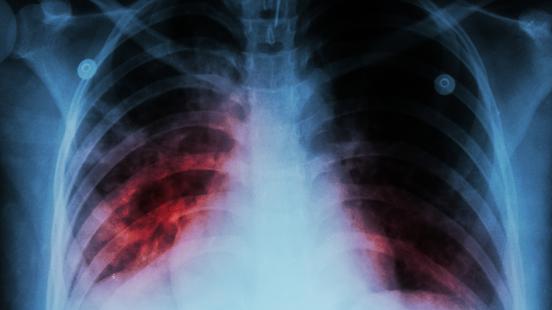

Brot de tuberculosi que afecta Barcelona i a altres municipis de l’Àrea Metropolitana de Barcelona. Segons ha avançat el Periódico, l’Agència de Salut Pública està avaluant els casos, 25 en total, que s’han diagnosticat principalment a la capital catalana i l’Hospitalet de Llobregat, i també a Terrassa, ha informat Món Terrassa. Podria tractar-se del brot més gran detectat a l’Estat els darrers anys.

Del total, 15 s’han detectat a la zona del Barcelonès Sud. S’ha confirmat la relació epidemiològica entre 10 d’aquests casos per vincles de proximitat geogràfica i un cas no resident a la mateixa zona, que treballava en un centre sanitari. L’estudi segueix en curs i és possible que es puguin associar més malalts, tant de manera retrospectiva com en el futur, ja que entre que una persona es contagia i comencen a aparèixer els primers símptomes poden arribar a passar 10 anys.

Tots els malalts s’han diagnosticat entre el 2022 i el 2204. Segons els epidemiòlegs, es pot tractar del brot més gran detectat a l’Estat dels darrers anys, recull el mitjà del grup Prensa Ibérica.